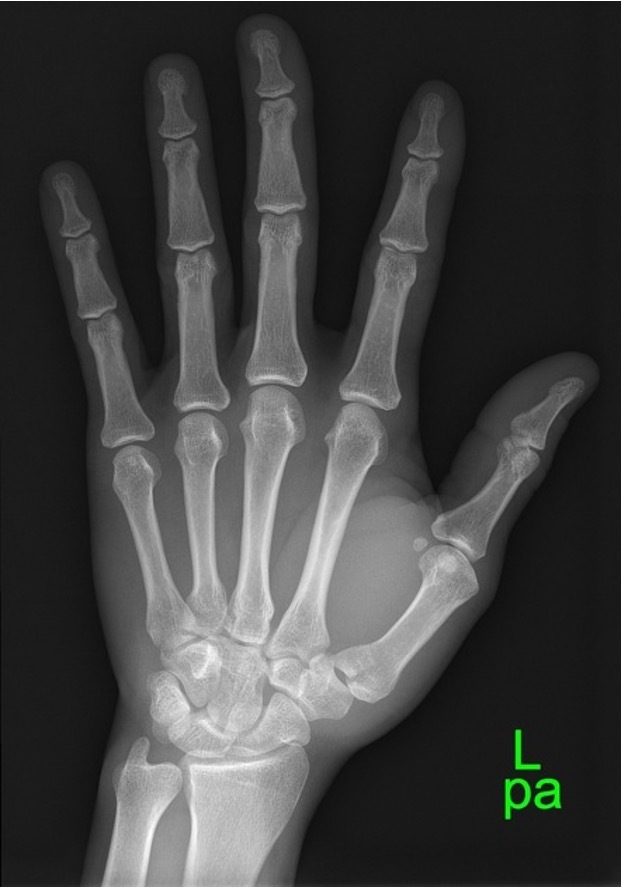

Intra-articular fracture-dislocation of the base of the 1st metacarpal bone (Bennett fracture)